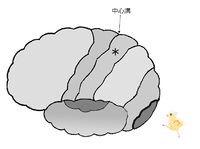

図は、左の大脳皮質を左から見た図です。

中心溝の前にある中心前回には、運動野があります。「手を挙げよう」などの随意的運動の命令は、前頭葉の中心前回に発生し、上肢、肩の筋へ届けられ手が挙がります。

中心溝の後ろにある中心後回には、(皮膚)感覚野があります。頭頂葉の一部です。皮膚から触圧覚・関節の感覚の情報は頭頂葉の中心後回に届いて「触った!」と感じるのです。

大脳皮質の図において、*印は 前頭葉 頭頂葉 後頭葉 側頭葉 である。